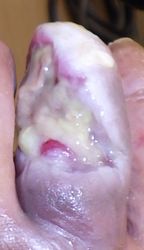

2018年2月4日,以前からhammer toe変形のあった左第2趾背側に潰瘍が発生。〇〇病院皮膚科を受診し,ユーパスタが処方されたが,治らないためフィブラストスプレー®⇒ゲーベンクリーム®⇒アクトシン軟膏®と次々に処方された。それでも治らないため,第2趾は根本で切断しか治療法はないと説明されている。

壊死組織を切除してズイコウパッドで創部被覆。以後は週に1〜2回の頻度で受診してもらい,そのたびに露出している腐骨を除去した。最終的には中節骨は全切除となったと思われる。